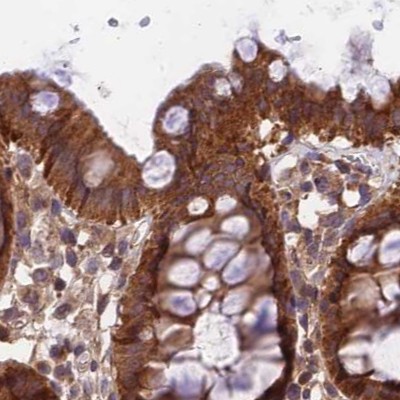

Immunohistochemical staining of human colon, kidney, testis and urinary bladder using Anti-MKKS antibody HPA041071 (A) shows similar protein distribution across tissues to independent antibody HPA044233 (B).